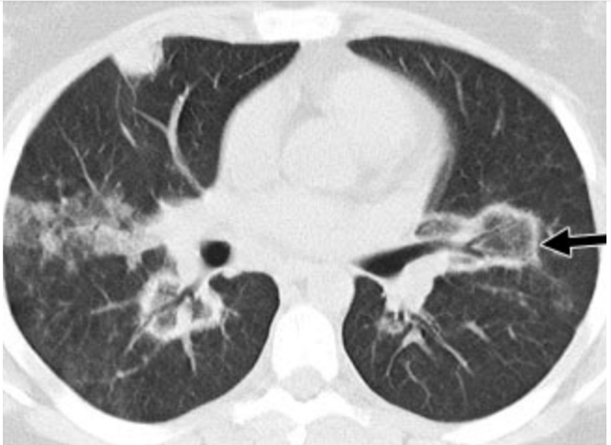

Na imagem de tomografia computadorizada (sem contraste venoso) abaixo, a seta preta aponta para uma área arredondada de opacidade em vidro fosco central circundada por um anel de consolidação do parênquima pulmonar.

Nas alternativas abaixo estão o nome do sinal (seta preta) segundo a “Fleischner Society” e alguns dos principais diagnósticos diferenciais. Assinale a alternativa correta.